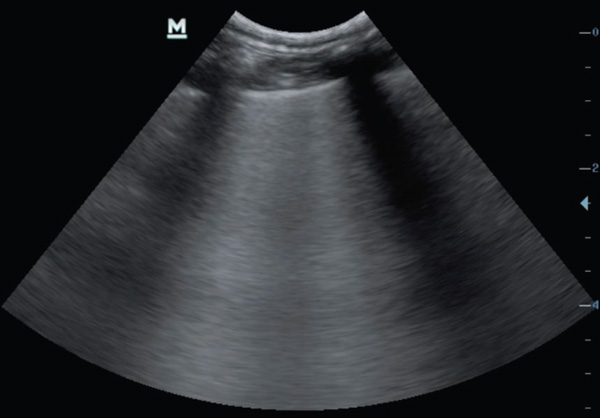

Point-of-care ultrasound is a tool to be used alongside the physical examination in the initial assessment of the dyspnoeic patient. No clipping is required, instead parting the fur and application of spirit to the skin should provide adequate contact for the probe. Placement of the probe in the rib spaces at numerous places dorsally and ventrally in numerous sites on both the left and right hemithorax will allow for assessment of pleural space disease and pulmonary disease. Pleural effusion and pericardial effusions can be identified easily as largely anechoic areas (Figure 3a). However, exudates may appear to be more echogenic. Ultrasound features of lung disease include the presence of ‘B lines’ or 'comet tails’ obliterating the normal ultrasound-gas interference (Figures 3b and 3c) With practice, cardiac chambers and the presence of a ‘glide sign’ can also be assessed on point-of-care ultrasound. Placement of the probe vertically between the ribs on the right hemithorax over the apex heartbeat allows visualisation for the four chamber view and then, with movement of the probe horizontally and cranially, the left atria to aorta ratio can be assessed. This requires practice and care should be taken to ensure correct chambers are identified before attempting a measurement. Increased left atria to aorta ratio suggests cardiac disease as strongly as the case of dyspnoea (Figure 4). A glide sign or ‘sliding lung’ represents the pleural-pulmonary line and in the absence of pleural space disease the lung glides along the thoracic wall as the patient breathes in and out. Absence of this line is suggestive of a pneumothorax.

Figure 3c. B lines